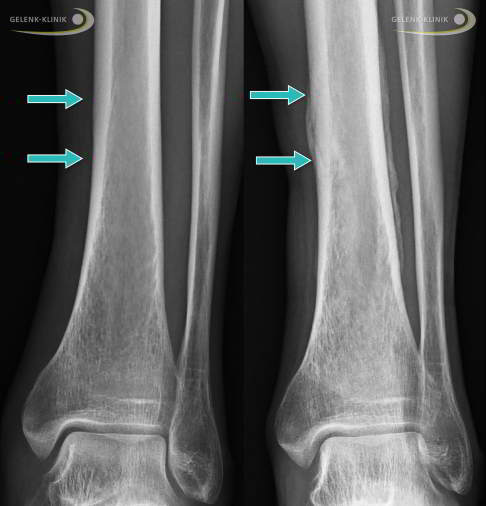

Stressfraktur des Schienbeins

Ermüdungsbrüche am Schienbein (Tibia) äußern sich sehr unterschiedlich. So kann beispielsweise das Periost (Knochenhaut) oder das im Knochen liegende Knochenmark als Stressreaktion Flüssigkeit einlagern (Ödem). Dies löst unspezifische Unterschenkelschmerzen aus. Nicht immer kommt es zu einer Verletzung der eigentlichen Knochensubstanz (Spongiosa) oder der härteren Außenschicht des Knochens (Kortikalis). Sind diese Strukturen betroffen, verläuft die Frakturlinie meist horizontal. Es können aber auch Längsrisse entlang des Schienbeinknochens auftreten. Die meisten Stressfrakturen treten im unteren (distalen) Bereich des Tibiaschaftes auf. Insgesamt betreffen etwa 50 % aller Stressfrakturen das Schienbein.

Nach der klinischen Untersuchung veranlasst der Arzt ein bildgebendes Verfahren, um die Situation der Knochen, Muskeln und Bänder beurteilen zu können. Die Diagnosesicherung ist dabei nicht immer leicht, da sich Knochenveränderungen durch Stressfrakturen im Anfangsstadium sehr variabel äußern. Röntgenbilder sind häufig nicht aussagekräftig. Meist sind erst zwei bis vier Wochen nach dem Auftreten erster Beschwerden feine Unterbrechungen der Knochenstruktur im Röntgen sichtbar. Erst später können Knochenverdichtungen, Bruchlinien oder Knochenhautreaktionen auftreten. Deshalb muss der behandelnde Arzt die Diskrepanz zwischen klinischen Beschwerden und einem noch unauffälligen Befund beachten, um bereits im Anfangsstadium die Diagnose Ermüdungsbruch stellen zu können.

Die vielversprechendste Möglichkeit zur Erkennung von Stressfrakturen im Bereich der Fußgelenke ist die digitale Volumentomographie (DVT). Dieses radiologische Verfahren macht Knochen- und Gelenkveränderungen durch die Erstellung von Schnittbildern bereits im Anfangsstadium der Erkrankung sichtbar. Häufig entstehen Stressfrakturen am Fuß im Bereich des Innenknöchels mit Beteiligung des Sprunggelenks, wo sie durch die DVT schon früh nach dem Auftreten erster Symptome erkannt werden können. Im Gegensatz zum MRT-Bild sind für die Diagnosestellung mittels DVT allerdings immer Veränderungen der Knochenstruktur notwendig, um Stressfrakturen sicher zu ermitteln. Das bildgebende Verfahren wird neben der Diagnostik auch zur Operationsplanung eingesetzt.